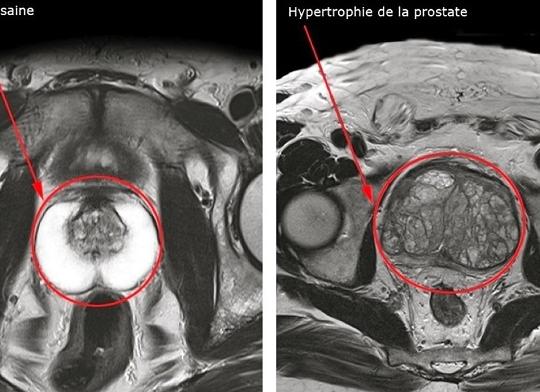

- Предстательная железа. Хорошо отображается только при введении контраста, который быстро распространяется по всему органу, имеющему четкие края. При развитии опухолей (рака, аденомы простаты) визуализируется дефект наполнения с ровными или нечеткими краями, деформирующими железу. Киста простаты имеет вид тонкостенной полости с жидкостью. При простатите орган увеличивается в размере, теряет четкость контуров, а контраст внутри нее распространяется медленнее.